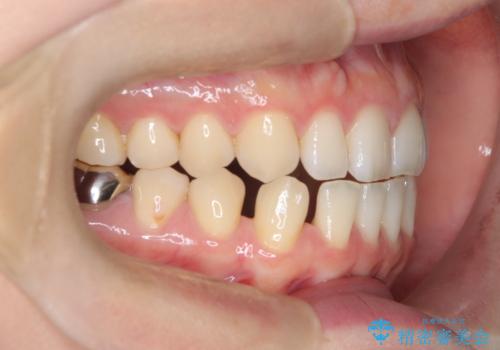

すきっ歯・切端咬合・空隙歯列|インビザラインで11ヵ月で治療完了

- すきっ歯と切端咬合(上下の前歯が先端で当たるかみ合わせ)を主訴にご来院された患者様です。

矯正検査を行った結果、非抜歯でインビザラインによる治療が可能と判断し、マウスピース矯正で改善を行いました。

11ヵ月で矯正治療が終了し、前歯の隙間も改善、見た目とかみ合わせも良好な状態となり、患者様にも大変ご満足いただけました。